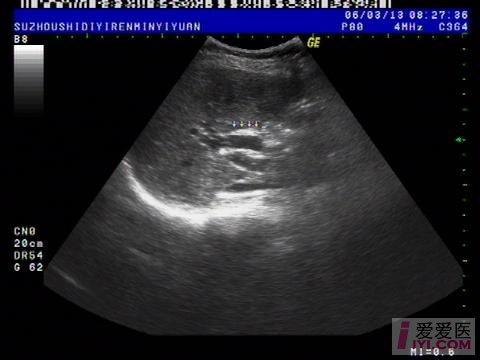

今天上午检查的一位病人, 胆囊切除术后会不会一定伴有胆总管扩张?

肝脏:左叶:长度47mm,厚度63mm 右叶:斜径106mm,形态规则,包膜完整,肝区光点细密,内部回声均匀,肝内血管走行清晰。 门静脉内径10mm。

胆囊:已切除。 胆总管:内径:11mm,胆囊窝未见积液。

1.肝未见异常。

2.胆总官扩张。